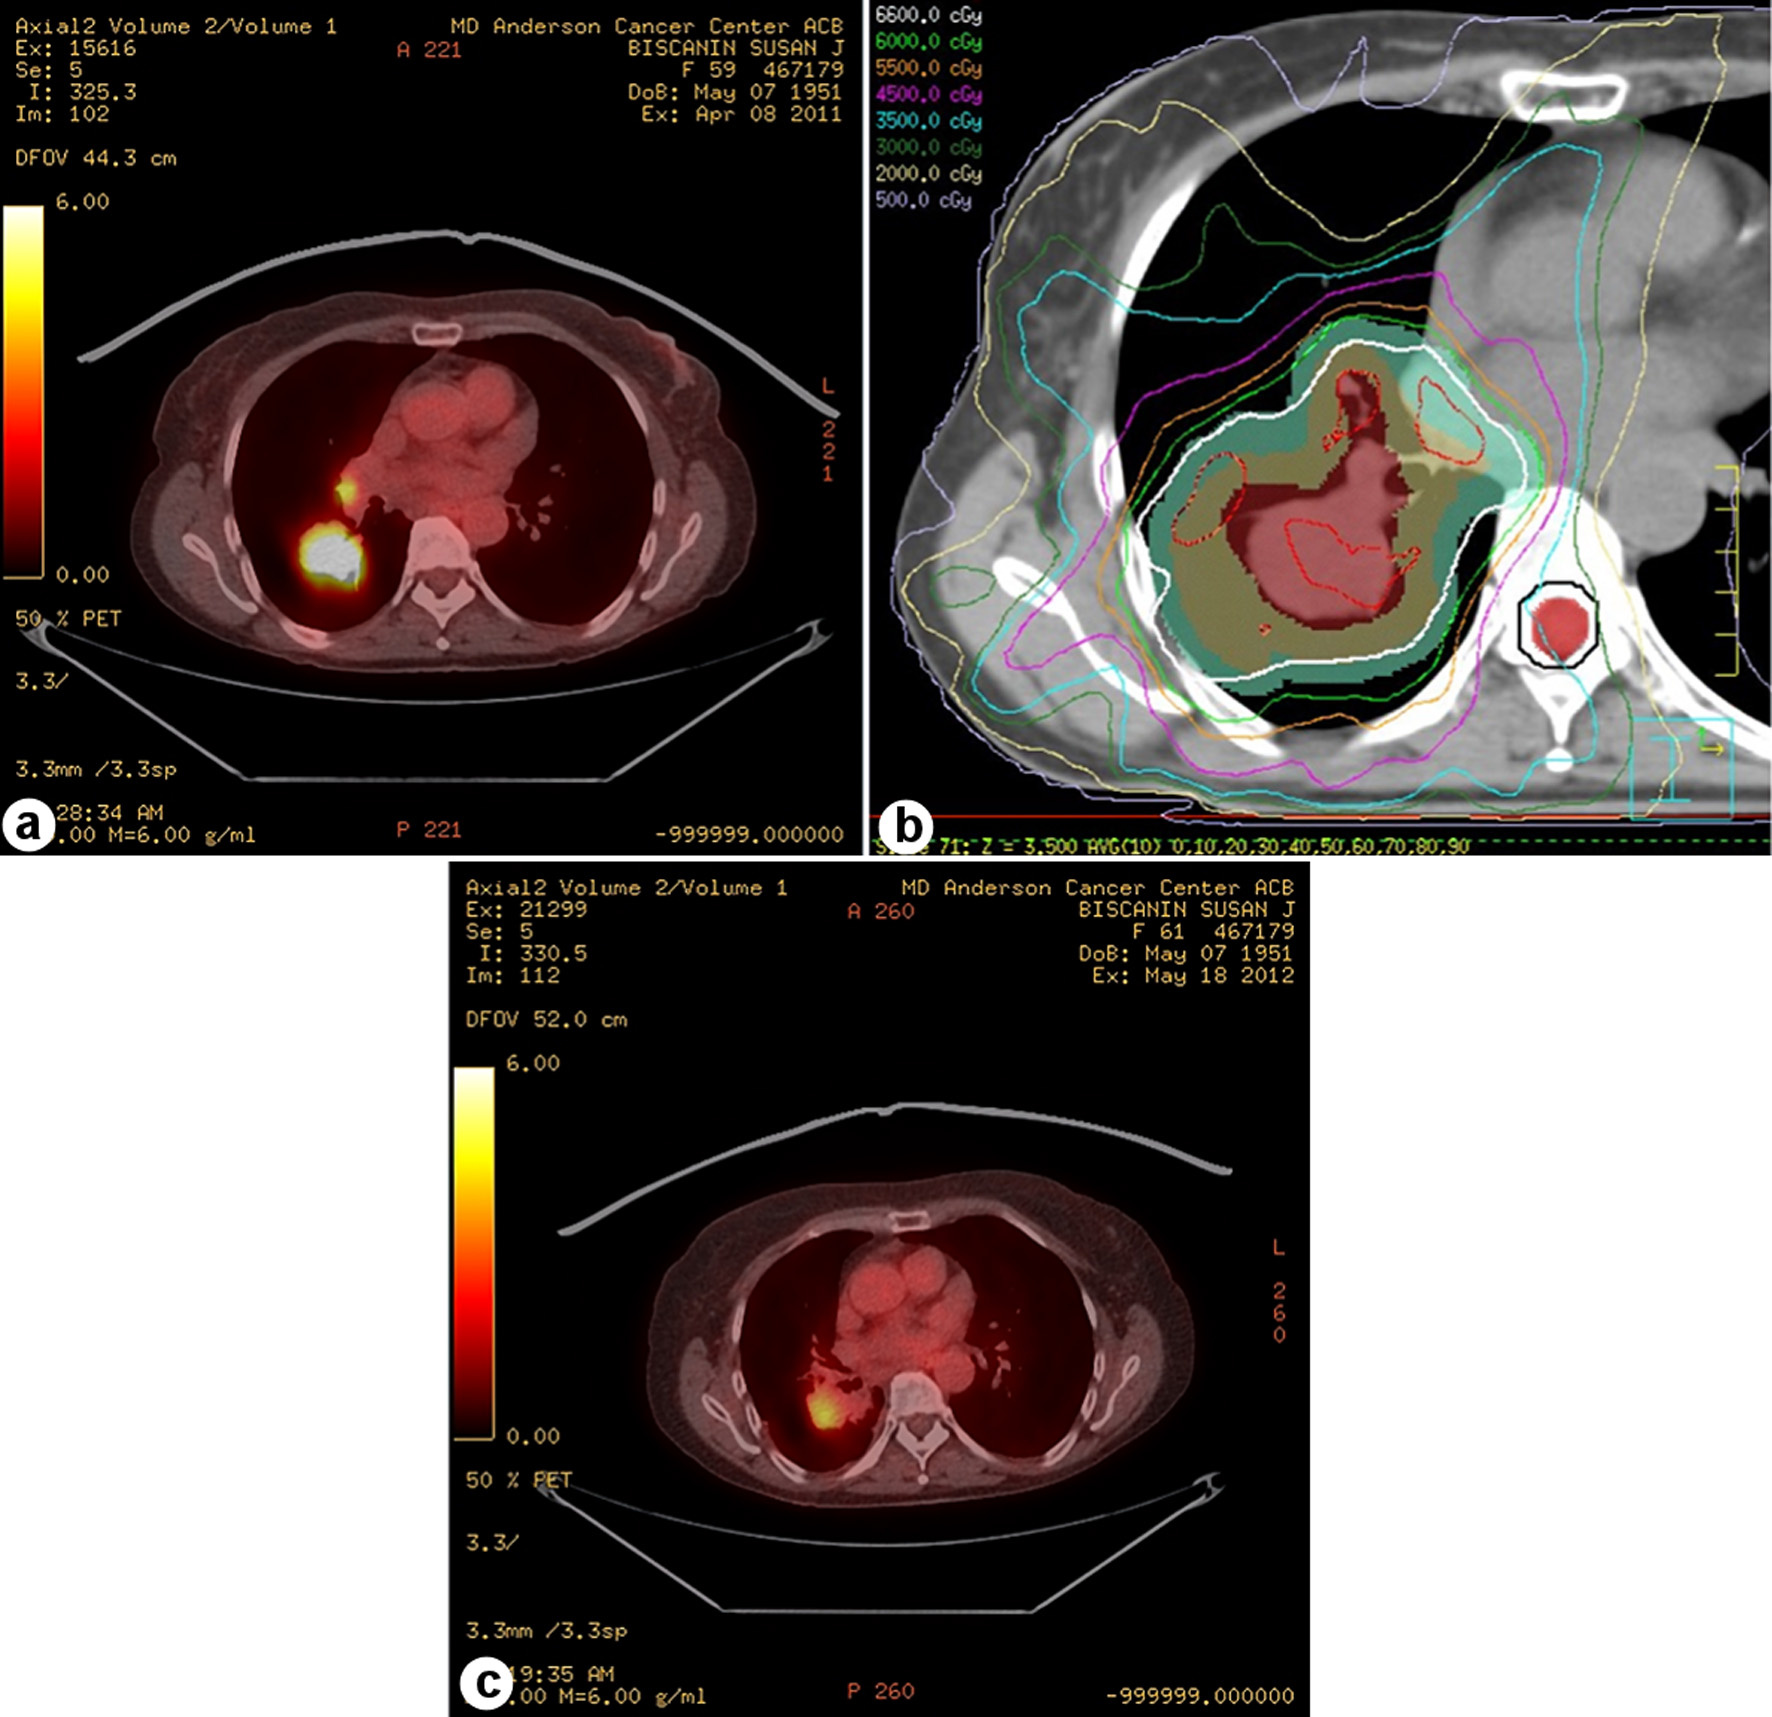

The characteristics of the 286 identified patients are shown in Table 1; 68 patients (24%) had local progression, the mean (± standard deviation (SD) patient age was 63.9 (± 10.4) years, and most patients (252, 88%) had stage III disease. The progression/no progression groups were relatively well balanced, except for age (patients without progression were slightly older than those with progression, P = 0.034), radiation modality (29% of those treated with photons had progression vs. 16% of those treated with protons, P = 0.02), and receipt of induction chemotherapy (32% of those who had received induction chemotherapy vs. 19% of those who had not received induction chemotherapy, P = 0.012). Mean radiation dose was similar between patients who did and did not experience local progression (68.1 ± 5.1 Gy or Gy (RBE) vs. 68.7 ± 6.5 Gy or Gy (RBE), P = 0.785). Although the SD values were large, the GTV was not different for those who did not experience progression. Most patients (262, 94%) received concurrent chemotherapy, but the progression rate was higher among those who received induction therapy (32%) than among those who did not undergo induction chemotherapy (19%, P = 0.02). The median follow-up time for the 68 patients with local progression was 57.4 months (range 1.27 - 93.5 months), and the mean interval to progression was 27 months (± 17.4 months (SD)). Among the patients who experienced local progression, EGFR mutations were detected in five of 67 patients (7%) and KRAS mutations in 14 of 60 patients (23%) (Table 1). Only one patient had mutations in both KRAS and EGFR and was excluded from the LPFS analysis. The PET and CT images of a representative patient with local progression are shown in Figure 1.

![]() Click for large image | Figure 1. Local tumor progression in a patient with stage III adenocarcinoma lung cancer. (a) Positron emission tomography (PET) image from diagnosis. (b) Intensity-modulated photon radiation therapy plan with isodose lines and planning target volume (PTV) in green colorwash. (c) Post-treatment PET scan shows local tumor progression inside the PTV. |